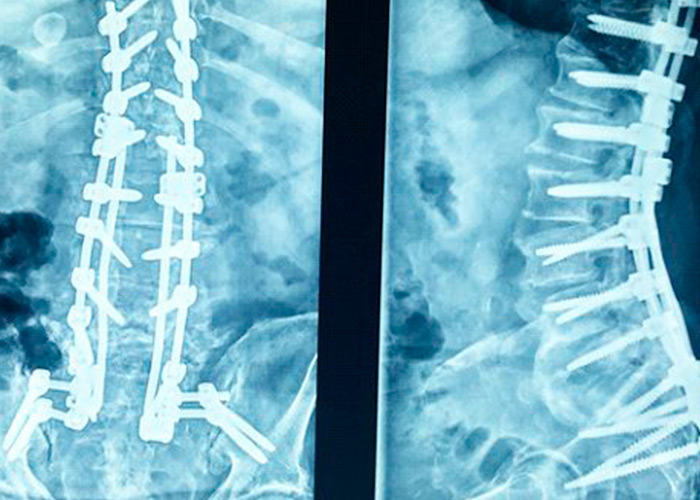

Varón de 58 años que acude a consulta con severa limitación funcional para la deambulación con inclinación y flexión postural  dorsolumbar. Presenta  antecedentes  quirúrgicos de artrodesis pedicular multinivel desde L5 a T10.

Preoperatorio

cirugia-de-columna-en-madrid-instituto-cac

preoperatorio-cirugia-de-columna-vertebral-en-madrid